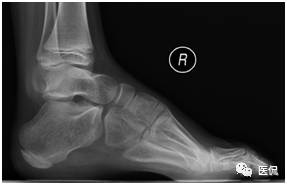

本病例临床病史示双足内翻、内收,呈马蹄状,X线整体观及个骨形态的改变与之相对应。负重X线侧位片显示足内弓减小,足外弓增大,舟骨发育不良,距舟关节半脱位,跟距角明显减小。

测量数据说明:测量的数据可反映病理改变及其程度,用以下角度加以说明。一是跟距角明显变小(正常值25-45度),严重者跟骨与距骨接近平行;二是跟骨倾斜角变小(正常值17-32度);三是距骨与第一跖骨向上成角,且大于4度。关于角度的测量,中轴线的定位尤为重要,不准确也会影响最终诊断。根据国外最新标准在原有标准基础上略有修改,更能准确客观的进行数据的测量,测量方法见后文。

足部负重侧位片:跟骨马蹄位,其上下径增大;舟骨外侧发育较小,距舟关节半脱位;即使强迫前足向背弯曲,其较后足仍向足底弯曲(弓形足);跟距角变小(正常25-45度),严重时跟骨与距骨中轴线近似平行。